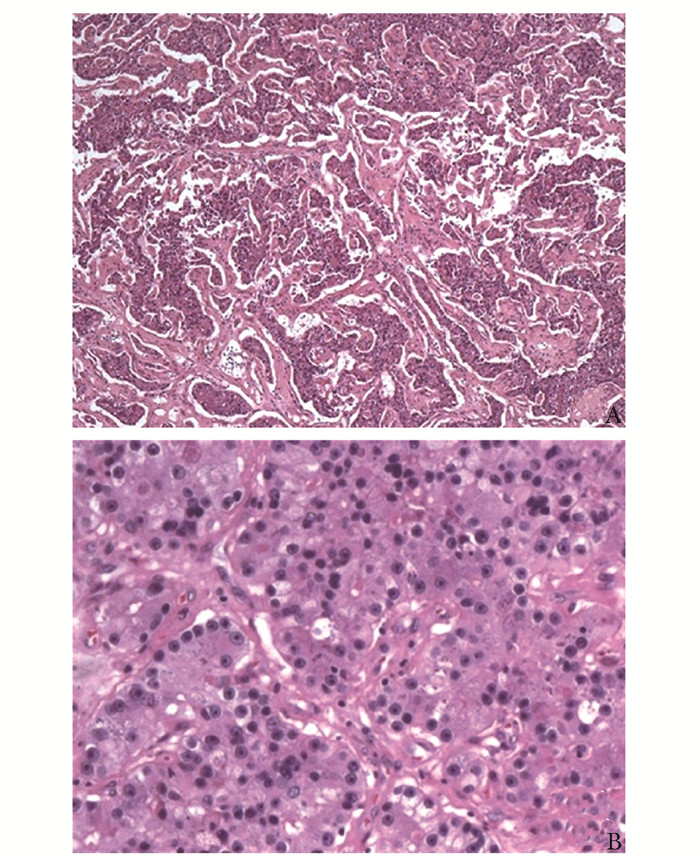

• 摘要: 肾细胞癌是泌尿系统中恶性度较高的肿瘤,常出现远端转移,尤其伴随中枢神经系统转移后,患者预后更差,临床管理困难,需多学科协作诊疗。本文报道一例肾透明细胞癌多系统转移患者,经北京协和医院肿瘤多学科协作团队(multidisciplinary team,MDT)5次会诊,得到个体化诊疗,并取得良好效果。通过对MDT讨论决策进行详细分析,可展现MDT在疑难重症病例诊疗方面的优势,有助于缩短治疗时间窗、打破科室界限、提高患者依从性、更好地制定符合循证医学理念的诊疗建议,为患者提供更加精准、个体化的临床管理方案。

Abstract: Renal cell carcinoma(RCC) is a type of tumor with a high degree of malignancy in the urological system, often with distal metastases, especially to the central nervous system. These patients are often endowed with poorer prognosis and more complex management that require a multidisciplinary team(MDT). This article reported a case of clear cell renal cell carcinoma with multisystem metastases.The MDT of Peking Union Medical College Hospital(PUMCH) discussed and formulated the optimal individualized treatment scheme for the patient, and achieved good results after 5 consultations. Through a detailed analysis of discussions and decisions of MDT, the advantages in the treatment of such difficult and serious cases are demonstrated, including shortening the time window of treatment, breaking down departmental boundaries, improving patients' compliance, developing treatment recommendations in line with the concept of evidence-based medicine, and providing more accurate and individualized clinical managements for patients.